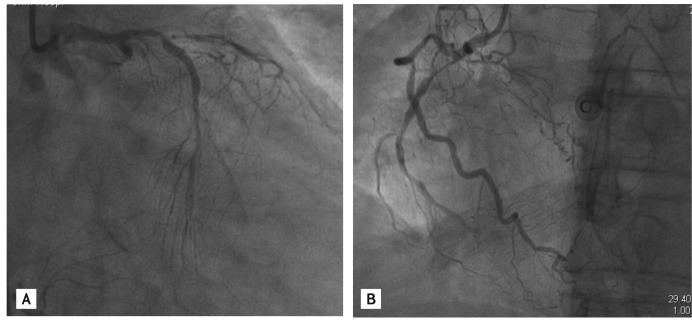

Figure 2

(A) A 3.0 × 28-mm Xience stent (Abbott Vascular) was implanted in the proximal right coronary artery. (B) The proximal segment of the left circumflex artery (LCX) was predilated initially using a 1.5 × 15-mm Ryujin balloon (Termo) to 10 atm. (C) The LCX lesion was predilated further with a 2.0 × 20-mm Ryujin balloon to 10 atm.